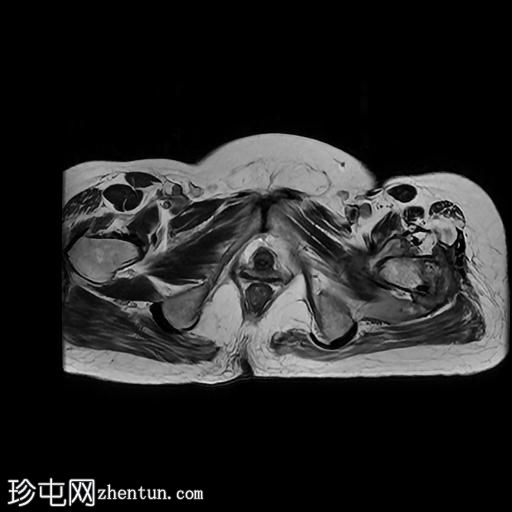

MRI

轴位

T2加权像

左髋关节存在严重的关节病变,表现为关节间隙显著变窄、软骨丢失、软骨下骨髓水肿以及囊性改变。

此外,左股骨颈基底部、股骨粗隆间区及股骨大转子区域可见骨髓信号异常及皮质破坏。伴有滑膜增厚及较大的冷脓肿腔,提示左股骨颈及股骨粗隆间区骨髓炎。

另一处较大的冷脓肿从股骨受损部位开始向上延伸至左侧臀肌。

在左侧股骨外侧皮下可见低信号窦道。